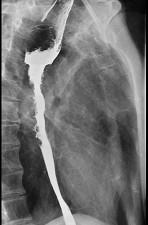

问题 女性患者,67岁进行性吞咽困难半年,X线及CT检查如图,应诊断为 ( )

选项 A.食管癌 B.食管憩室 C.食管炎 D.食管良性狭窄 E.食管静脉曲张

答案 A